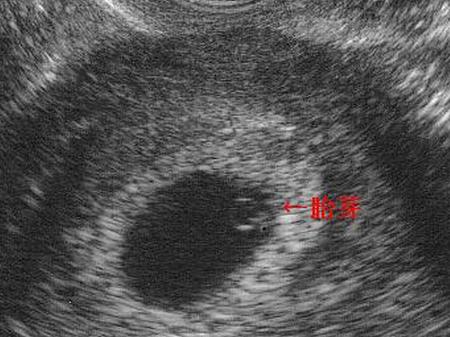

在早孕期,由于胚胎比较小,在超声检查下仅可以看到妊娠囊内一个类似于胚芽一样的影像,被称为胎芽。在B超检查时能看到胎芽的时间大概是40-50天左右。

妇科B超可以分为经阴道B超以及经腹部B超,相对于经腹部B超检查,经阴道B超检查可以更早的看到妊娠囊以及胎芽、胎心,时间大概可以早5-7天。因此,如果通过经阴道B超检查,在孕5周的时候就可以看到胎芽,也就是停经35天后就可以看到胎芽了。而经腹部B超检查可能就需要到6周左右。